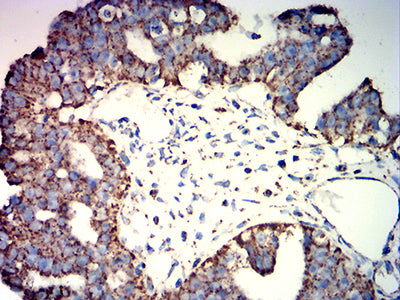

Immunohistochemical analysis of paraffin-embedded human lung cancer tissues using ATP5F1A mouse mAb with DAB staining.

Immunohistochemical analysis of paraffin-embedded human ovarian cancer tissues using ATP5F1A mouse mAb with DAB staining.